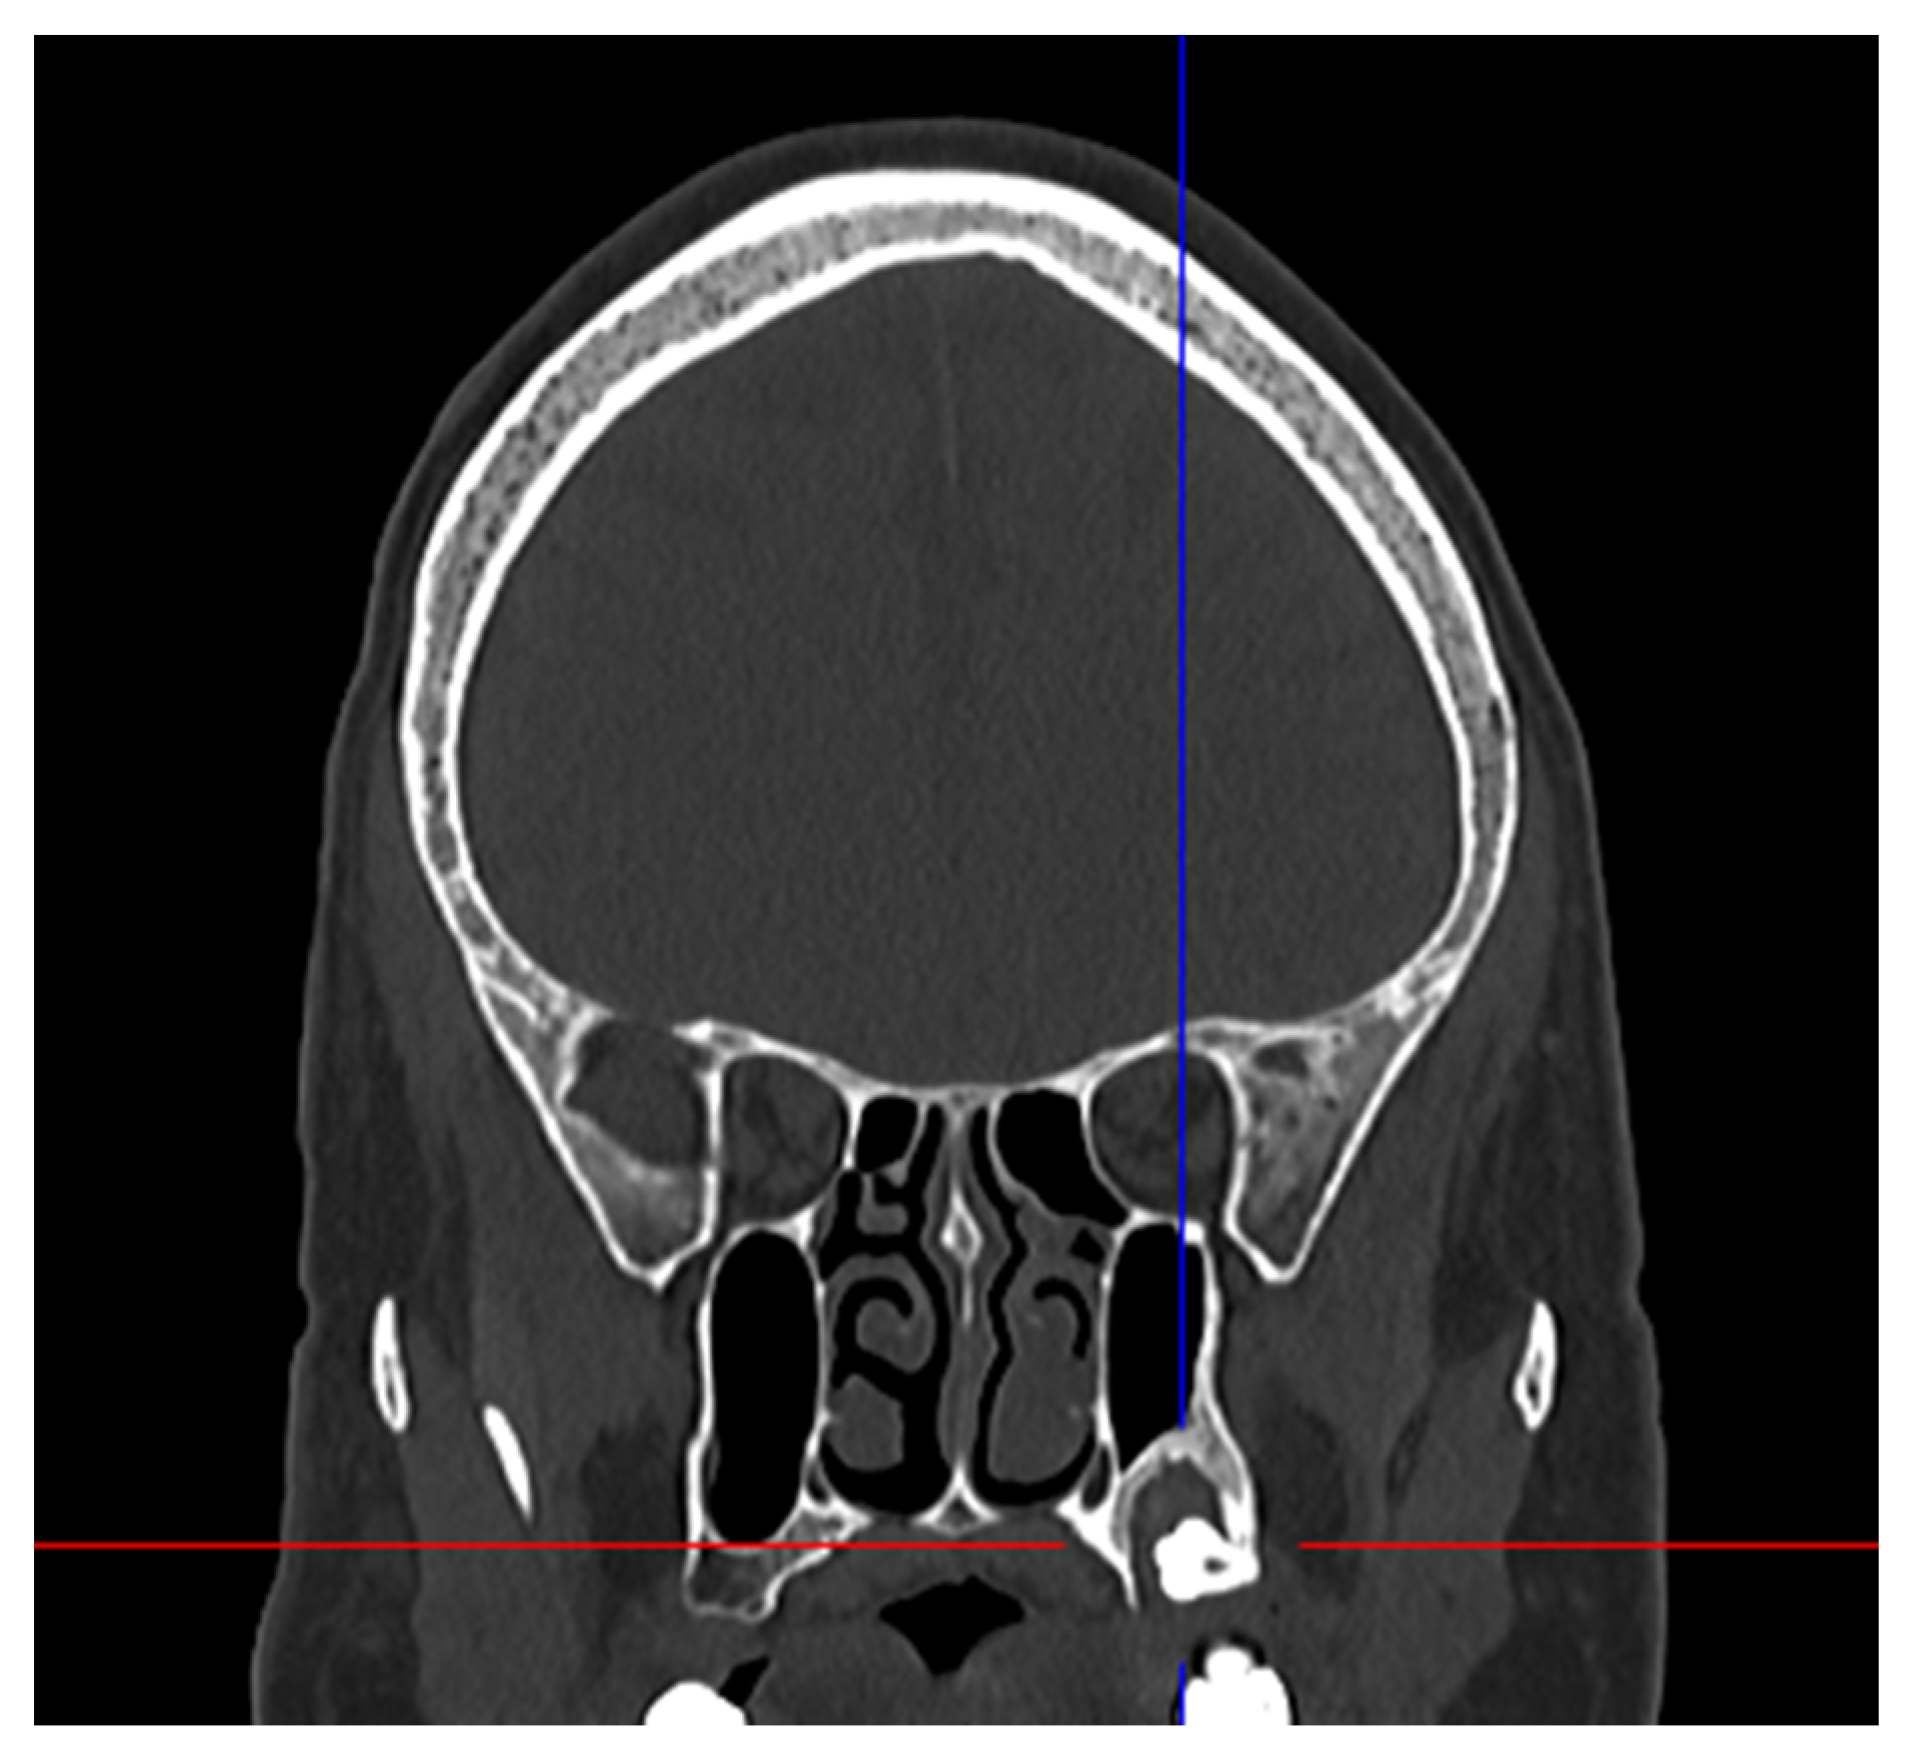

2. Case Presentation

| Present Case | M | 46 | Pain | Maxillary distomolar | Enucleation |